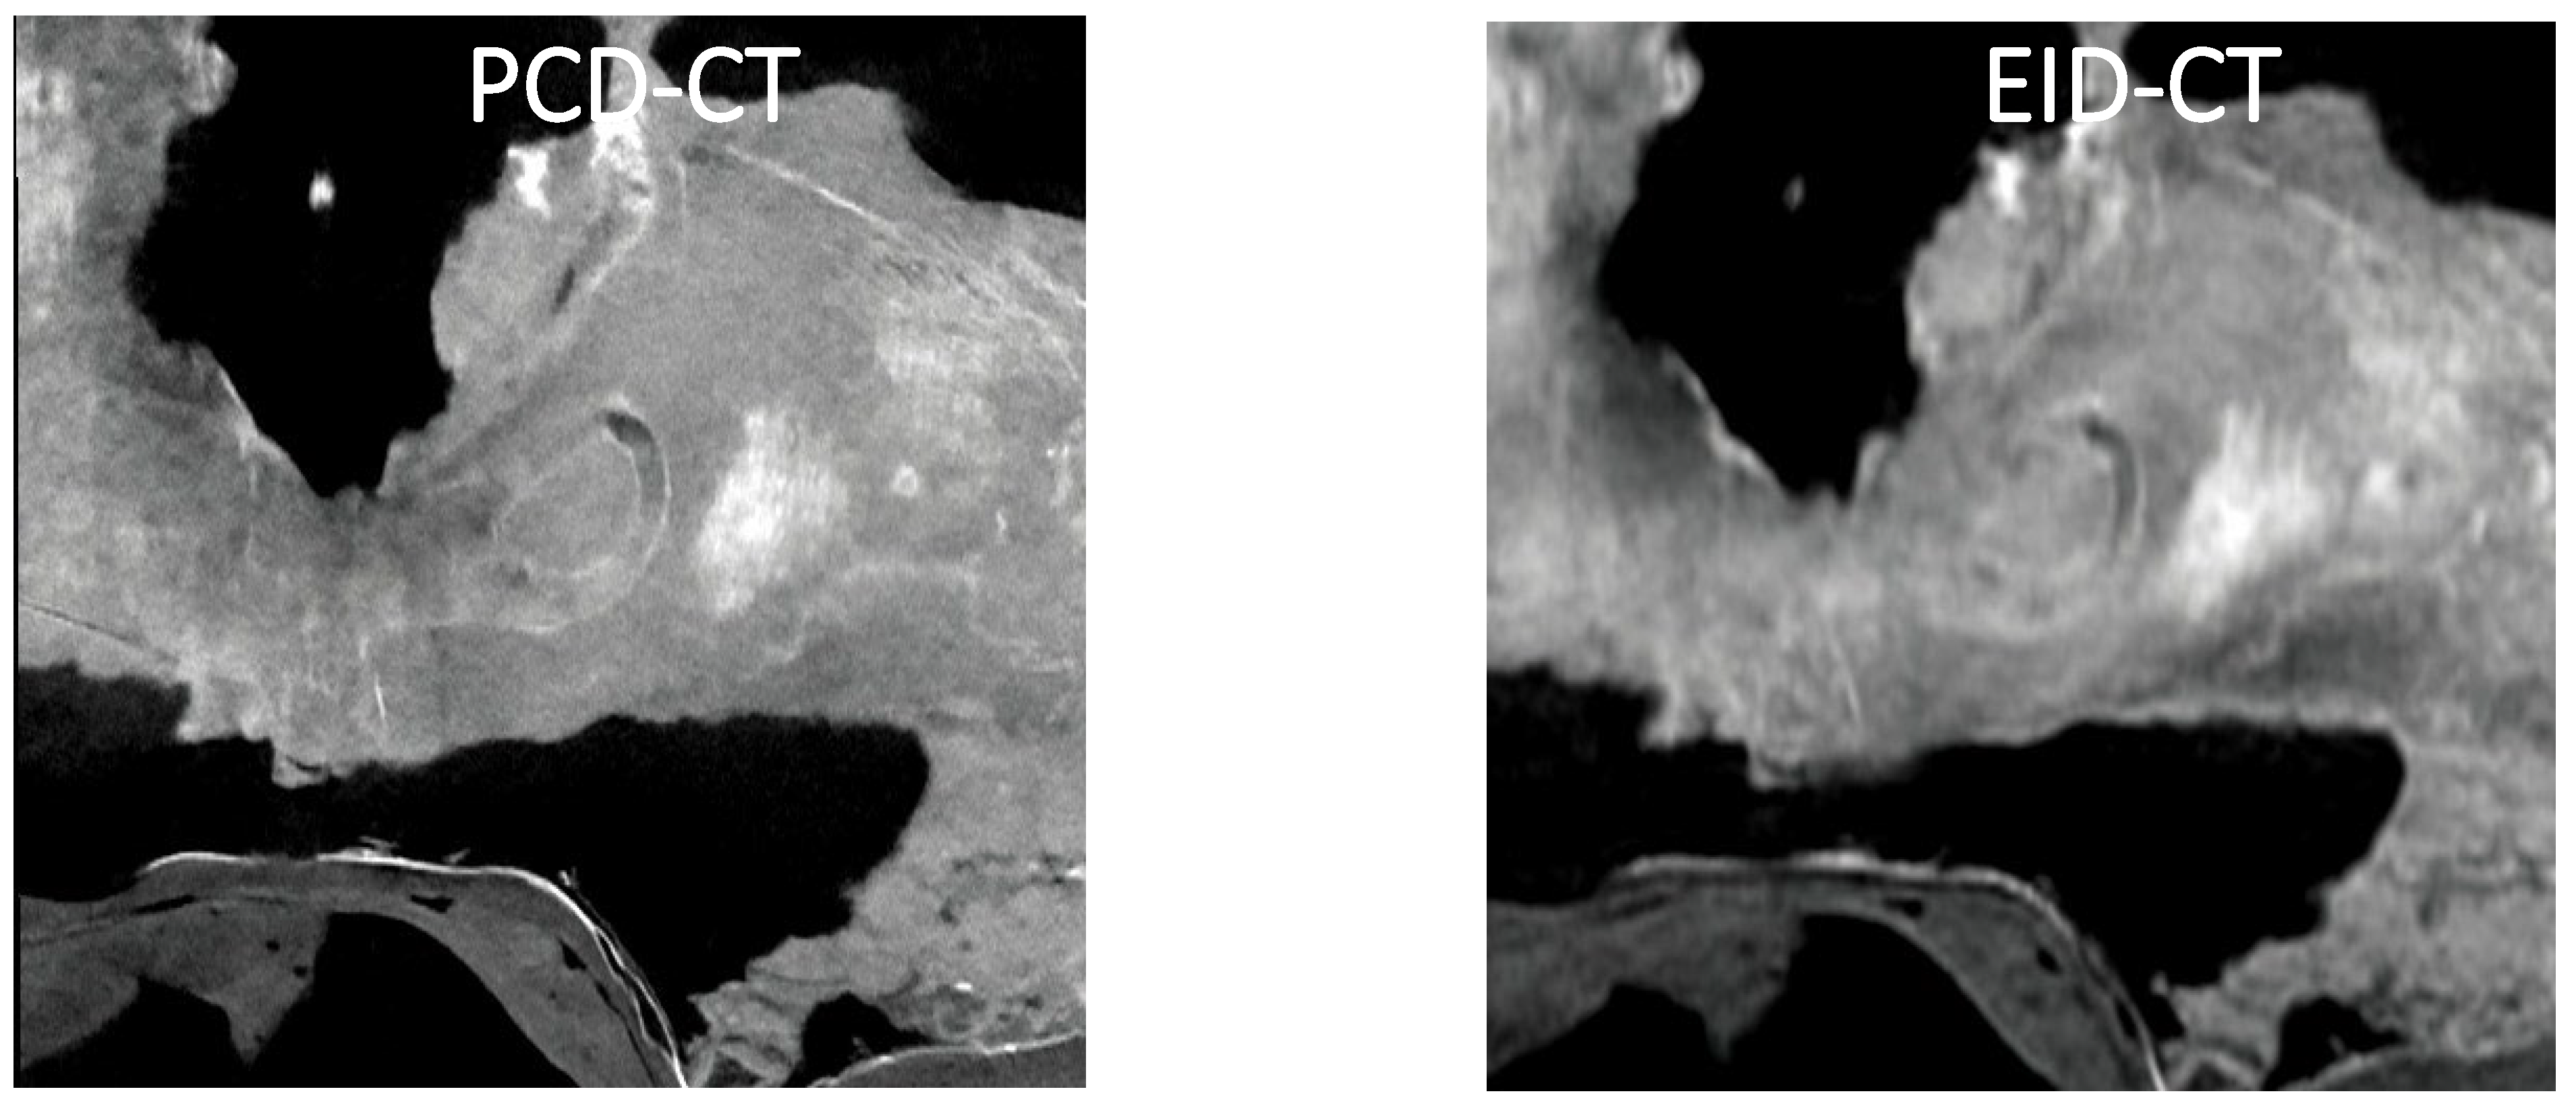

Figure 2A,B show the sagittal sections of the Tyrannosaurus lower jawbone imaged with PCD-CT and EID-CT, respectively. Compared with EID-CT, PCD-CT more clearly depicts the cross-sectional patterns and the mandibular canal including a hyper-dense structure.

Figure 2. Sagittal sections of the Tyrannosaurus lower jawbone imaged with PCD-CT and EID-CT.

To the best of our knowledge, this is the first photon-counting CT imaging study of dinosaur fossils. This study demonstrates the significant advantages of PCD-CT over conventional EID-CT in imaging dinosaur fossils. The superior spatial resolution and contrast-to-noise ratio of PCD-CT allow for more detailed visualization of fossil internal structures such as the Tyrannosaurus mandibular canal and the semicircular canals of the Camarasaurus. Visualizing fine anatomical details with PCD-CT creates new possi-bilities for paleontological research. For example, detailed images of the mandibular canal in the Tyrannosaurus fossil may provide new information on the sensory capabilities and feeding behavior of this iconic dinosaur [13]. Similarly, the clear imaging of the semicir-cular canals in the Camarasaurus fossil may shed light on the balance and locomotion of this large sauropod.